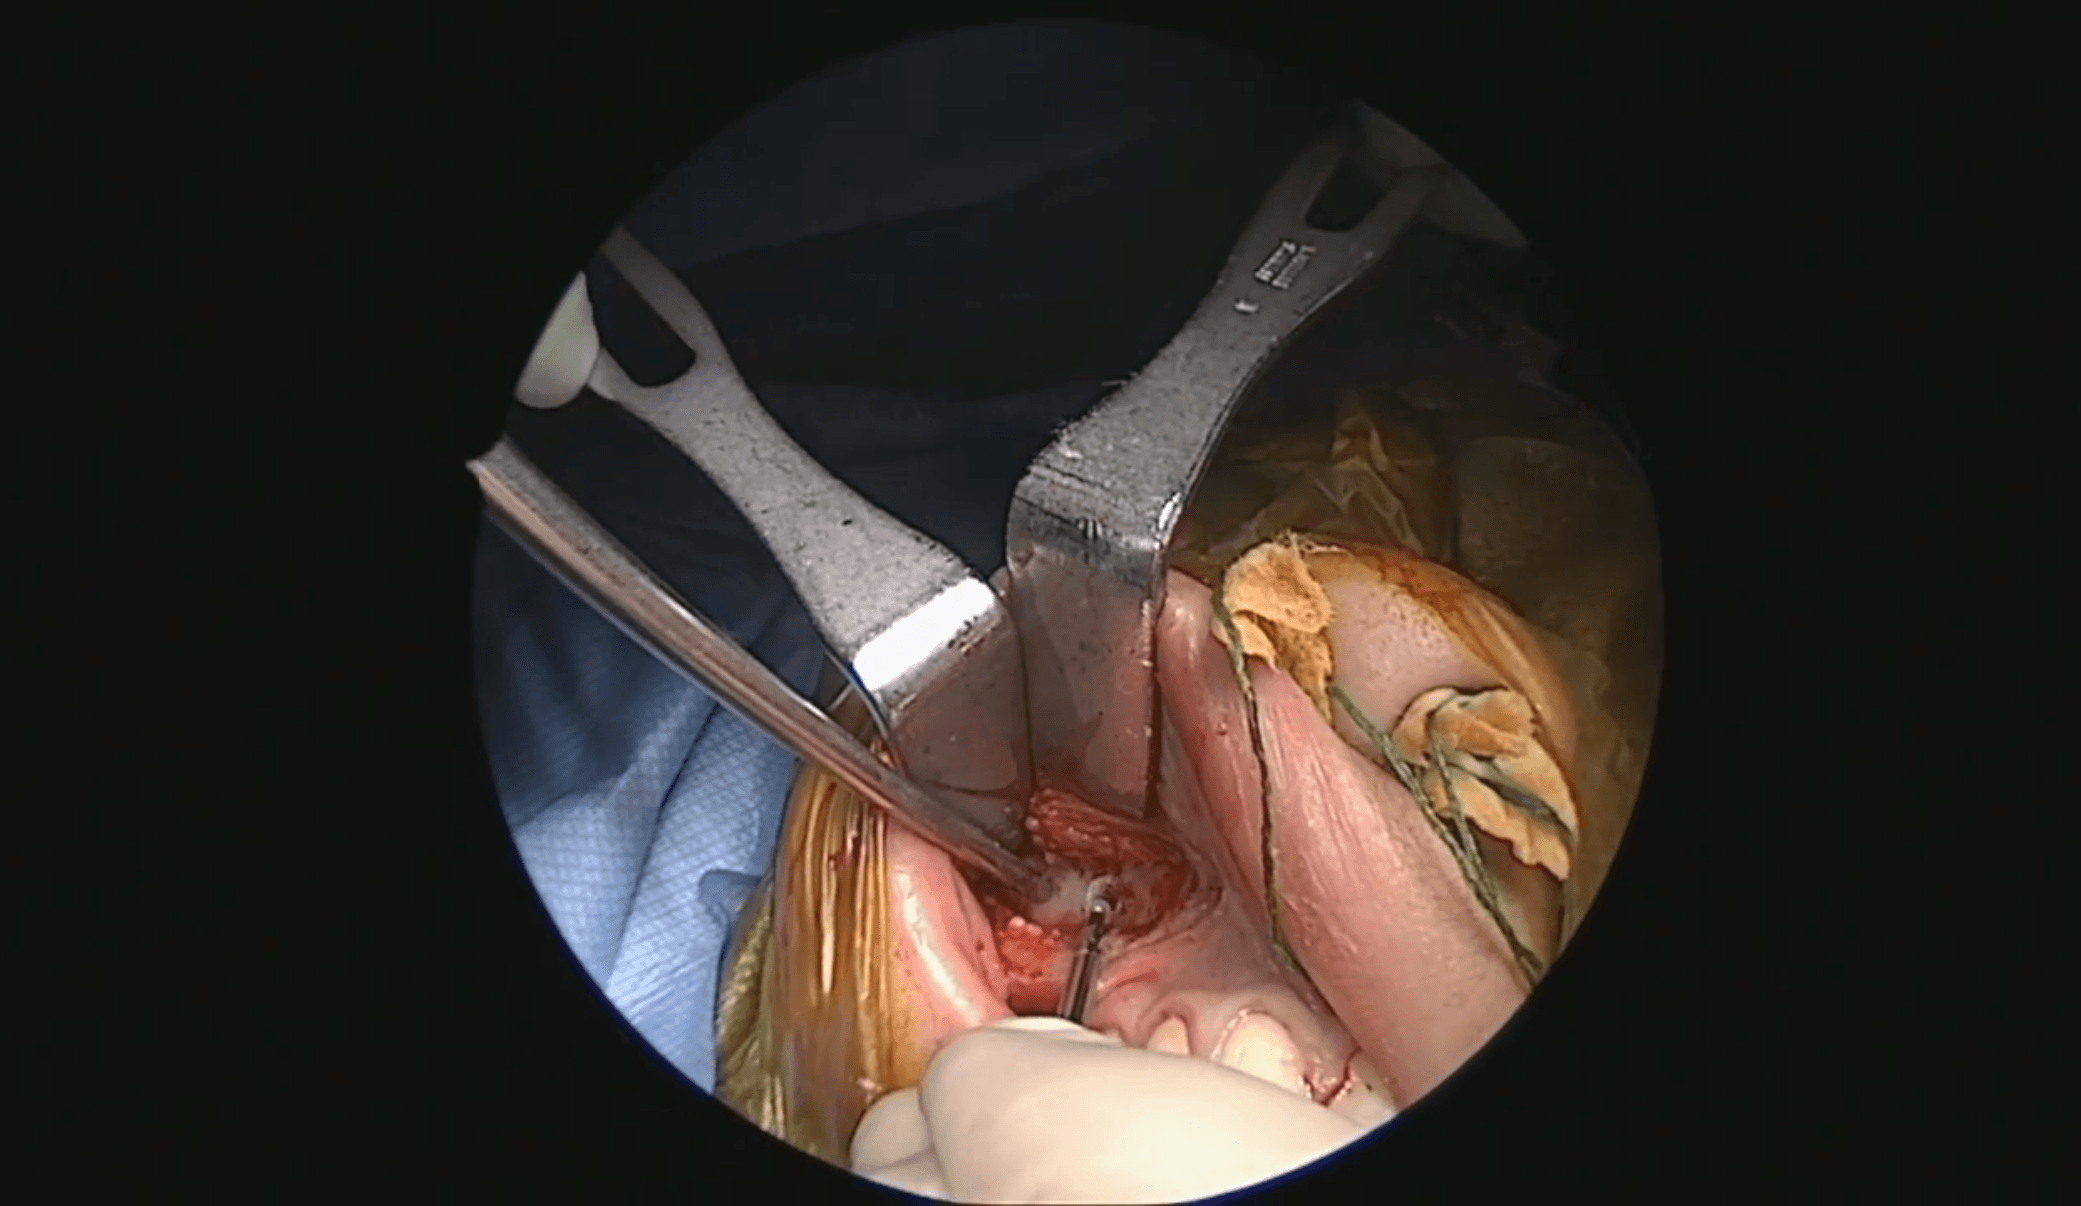

Abordaje quirúrgico combinado

El Dr. Carlos Pinheiro Neto emplea una estrategia combinada:

- Abordaje sublabial derecho con apertura amplia de seno maxilar y fresado de pared posterior (caudal look transmaxilar).

- Abordaje endoscópico endonasal bilateral con etmoidectomía anterior y posterior, esfenoidotomía amplia y septectomía posterior.

La justificación técnica es clara: el componente nasal y esfenoidal se aborda endonasalmente, mientras que la extensión lateral a fosa infratemporal se controla mejor desde un corredor transmaxilar inferior y lateral. Esta doble vía evita traccionar el tumor “a través” de sí mismo y permite disección circunferencial.

En paralelo, el abordaje transmaxilar permite identificar precozmente la arteria maxilar interna. En este caso, al estar embolizado, el Dr. Pinheiro Neto opta por cauterización directa (habitualmente emplea clips). El control vascular temprano reduce pérdida hemática y mejora el plano de disección.

La disección en fosa infratemporal es progresiva, cauterizando y seccionando adherencias a musculatura pterigoidea lateral. La adherencia muscular es intensa en JNA avanzados y requiere disección meticulosa, evitando desgarros que comprometan la hemostasia.